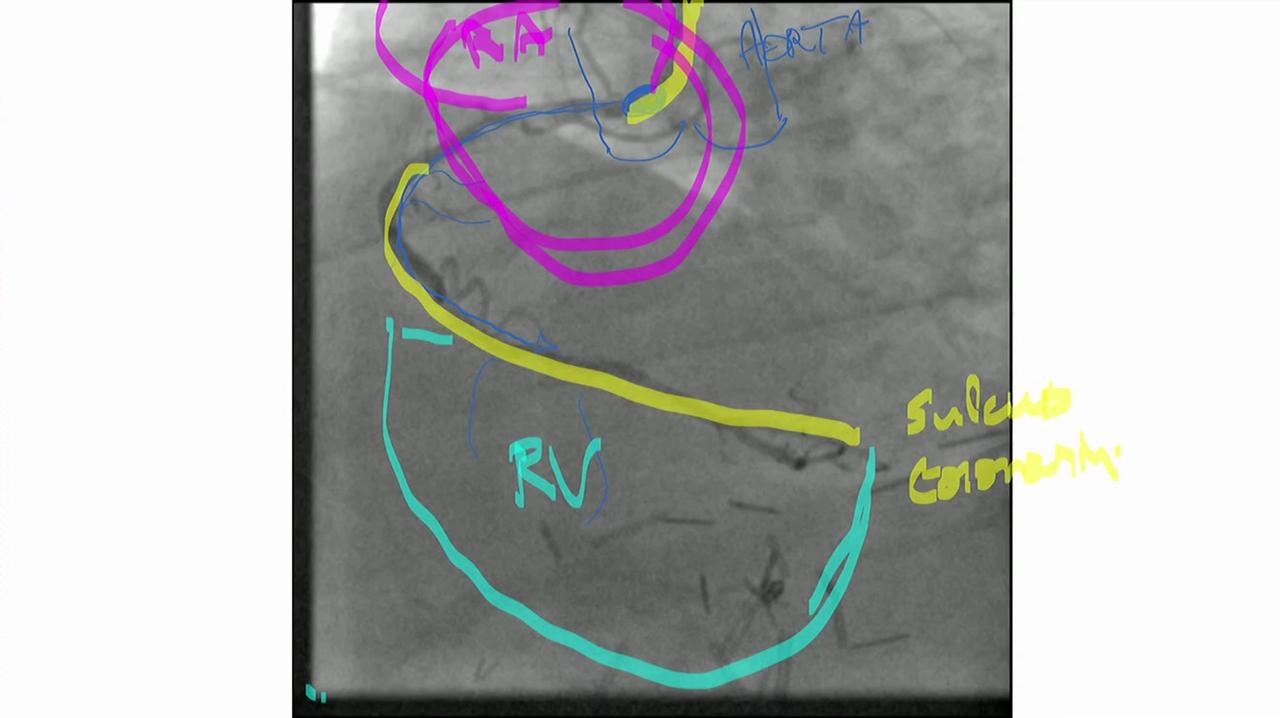

Interactieve les - a. coronaria dextra

aorta

atriun dextrum (RA)

ventriculus dexter (RV)

sulcus coronarius

ventriculus sinister (LV)

a coronaria dextra, r. interventricularis posterior (rood)